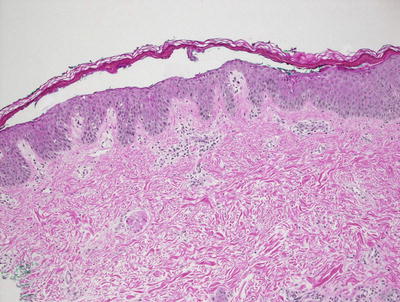

3.9.2 Histology

Histologic features of Hailey–Hailey disease show an epidermis with varying degrees of spongiosis and acantholysis. The stratum corneum has normal thickness. The roof of the intraepidermal blister is often fragmented with single keratinocytes separating from other keratinocytes, the so-called “dilapidated brick wall” appearance (Figs. 3.21 and 3.22). Dyskeratotic cells are not abundant. An inflammatory infiltrate that is predominantly lymphohistiocytic with scattered eosinophils is present and may extend into the epidermis [63, 64].

Fig. 3.21

Hailey–Hailey disease shows a mid-epidermal or suprabasilar blistering process within a spongiotic epidermis